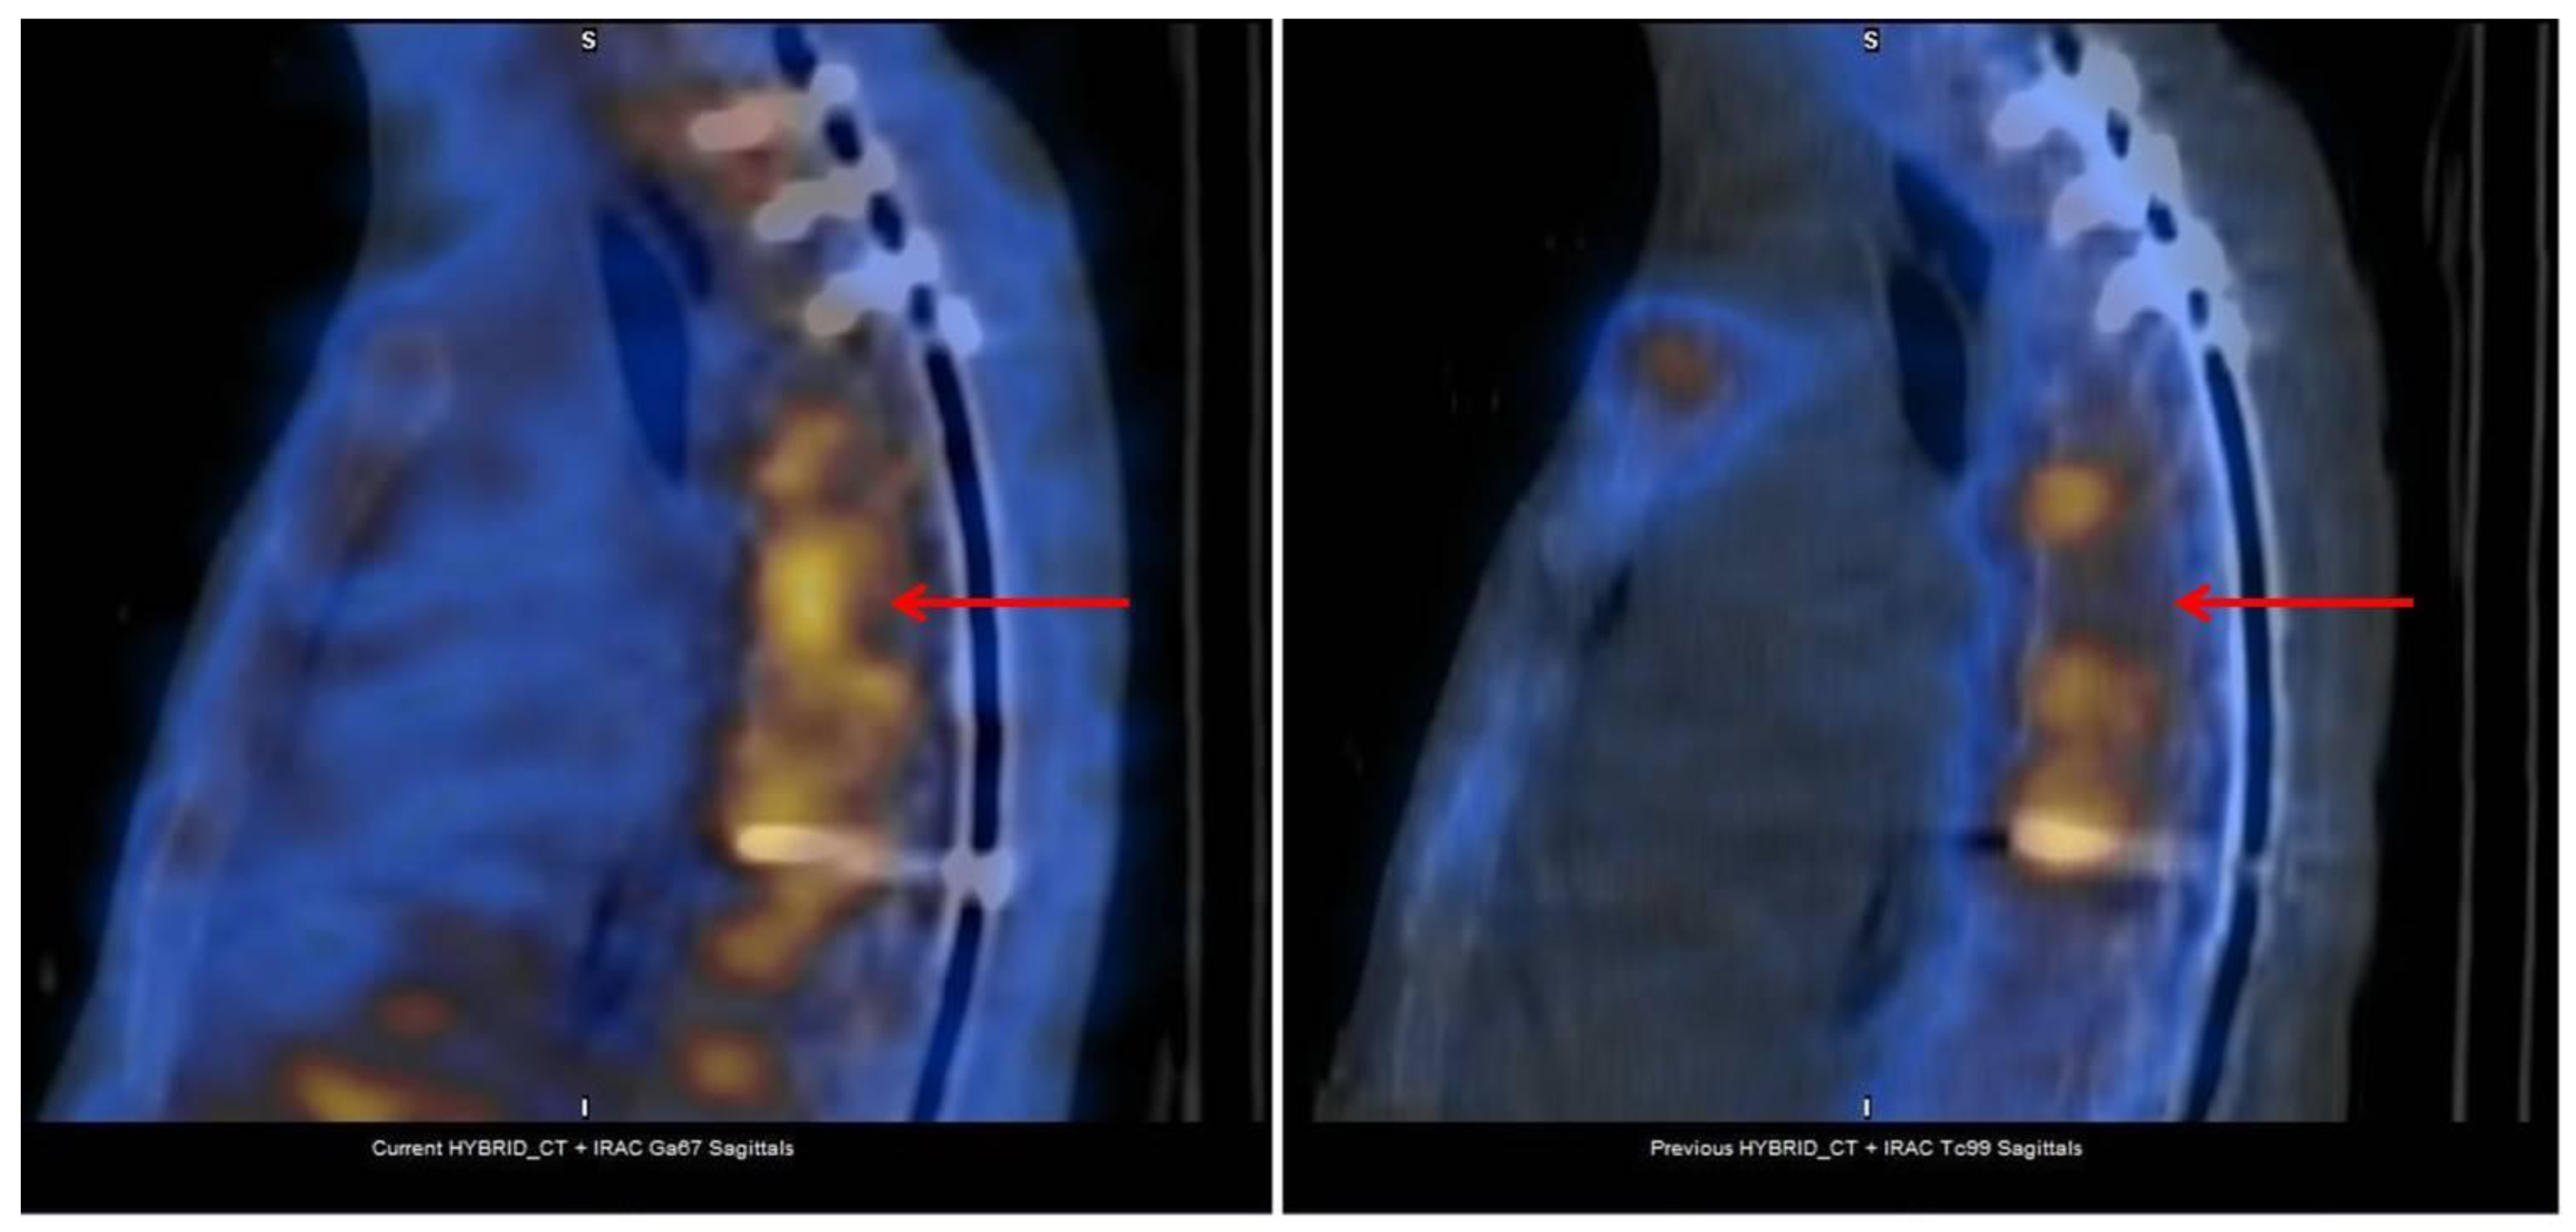

5. Monitoring Musculoskeletal Infections: The Role of NM

- Dauchy, F.A.; Dutertre, A.; Lawson-Ayayi, S.; de Clermont-Gallerande, H.; Fournier, C.; Zanotti-Fregonara, P.; Dutronc, H.; Vital, J.M.; Dupon, M.; Fernandez, P. Interest of [(18)F]fluorodeoxyglucose positron emission tomography/computed tomography for the diagnosis of relapse in patients with spinal infection: A prospective study. Clin. Microbiol. Infect. 2016, 22, 438–443. [Google Scholar] [CrossRef] [PubMed]

- Nanni, C.; Boriani, L.; Salvadori, C.; Zamparini, E.; Rorato, G.; Ambrosini, V.; Gasbarrini, A.; Tumietto, F.; Cristini, F.; Scudeller, L.; et al. FDG PET/CT is useful for the interim evaluation of response to therapy in patients affected by haematogenous spondylodiscitis. Eur. J. Nucl. Med. Mol. Imaging 2012, 39, 1538–1544. [Google Scholar] [CrossRef]

- Russo, A.; Graziano, E.; Carnelutti, A.; Sponza, M.; Cadeo, B.; Sartor, A.; Righi, E.; Bassetti, M. Management of vertebral osteomyelitis over an eight-year period: The UDIPROVE (UDIne PROtocol on VErtebral osteomyelitis). Int. J. Infect. Dis. 2019, 89, 116–121. [Google Scholar] [CrossRef]

- Righi, E.; Carnelutti, A.; Muser, D.; Di Gregorio, F.; Cadeo, B.; Melchioretto, G.; Merelli, M.; Alavi, A.; Bassetti, M. Incremental value of FDG-PET/CT to monitor treatment response in infectious spondylodiscitis. Skeletal Radiol. 2020, 49, 903–912. [Google Scholar] [CrossRef]